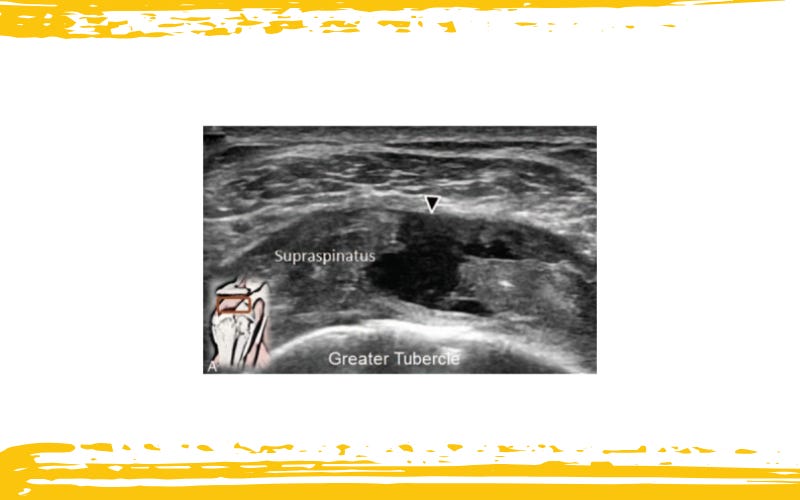

Imágenes ecográficas de:

(A) rotura de espesor completo del tendón del supraespinoso,

La ilustración situada en la esquina inferior izquierda representa la posición del transductor. Las flechas señalan los sitios de la rotura.